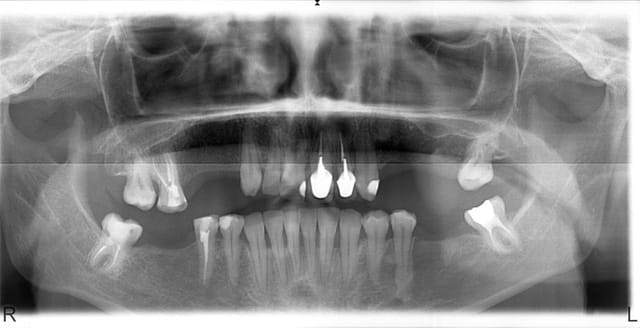

Finalement patiente revenue 8 ans plus tard et finalisée par endos, paro stellites...

Désolé je n'ai pas de belles photos de greffes osseuses comme D57 ou mes collègues implanto...

(la 22 est quasi cicatrisée pour les observateurs)